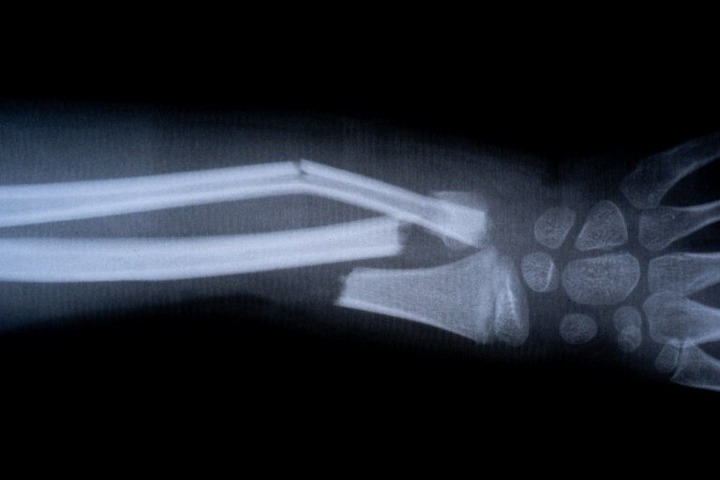

JUST IN: Chinese scientists develop ‘bone glue’ that heals fractures in minutes

Scientists in China have unveiled a groundbreaking “bone glue” that can heal fractures within minutes, cutting down recovery times that would normally take months. The product, called Bone-02, was developed by a research team aiming to reduce the need for invasive orthopedic surgeries that often involve metal plates and screws, according to New York Post.